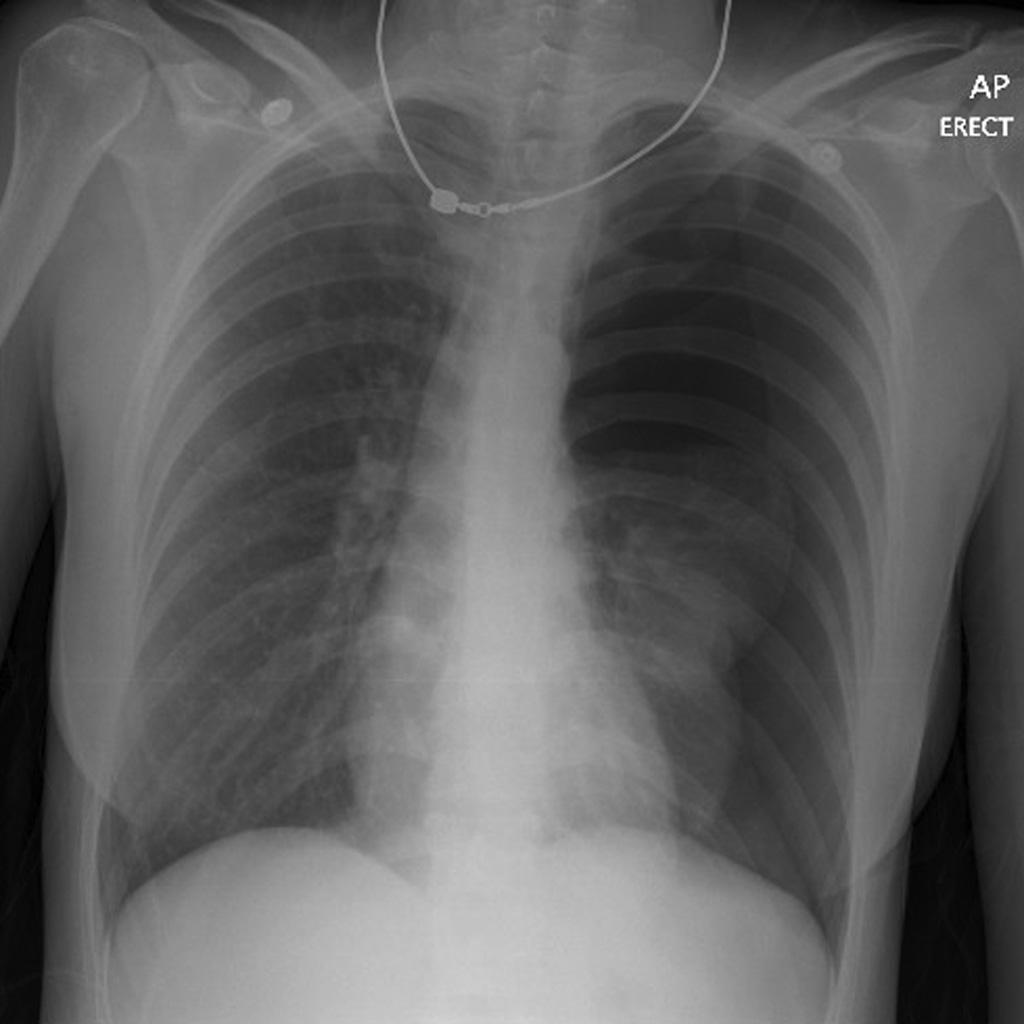

Take a look at the following example. Let us go through how we would systematically analyse this and the diagnosis.

D – This is a Chest X-Ray taken on ….., of the following patient….. Is there a previous CXR to compare to

R – Commenting first on the quality, it is not rotated, there is adequate inspiration, the projection is posterior-anterior and it is adequately exposed as I can see the vertebral bodies clearly

“On initial inspection, there appears to be increased luceny on the left side and a central line in situ, but I will proceed to go through it systematically.”

A – Starting with the airways, the trachea is deviated to the right, and the carina is visible.

B – On the left side, the pleural markings do not go all the way to the costal margin. There is increased lucency in the left upper zone which is suggestive of a pneumothorax. There is no evidence of any consolidation.

C – The heart is not enlarged and the heart borders are clearly visible.

D – The hemidiaphragms are clearly visible and there is no blunting of the costophrenic angles. There is no free air under the diaphragm.

E – There appears to be a tunnelled line which has its tip in the right atrium.

There is no abnormality in the review areas, including the apices, behind the heart.

In summary the key finding is left sided pneumothorax.

Left Sided Pneumothorax